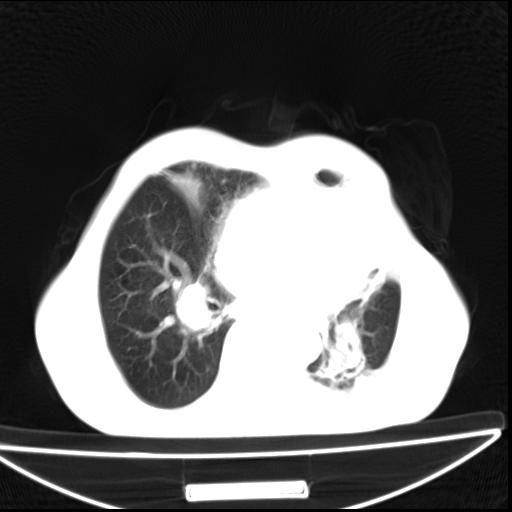

男  70岁,发烧咳嗽4天。盗汗,消瘦。无痰中带血丝,以前有肺tb病史,ct见,双肺tb,左侧胸廓塌陷,左胸膜肥厚粘连。纵隔移位,右侧胸腔积液,大家说说那个心影前左肺舌叶除了肺大炮还有炎症还是干酪性肺炎?有占位吗?我看纵隔淋巴结也大。

1)两肺继发性肺结核并左肺上叶肺不张,支气管扩张。2)双侧胸膜炎(胸膜增厚+少量胸腔积液)。

双肺继发性肺结核伴部分左肺毁损!

两肺继发性肺结核并感染,左肺上叶肺不张。建议ct增强。